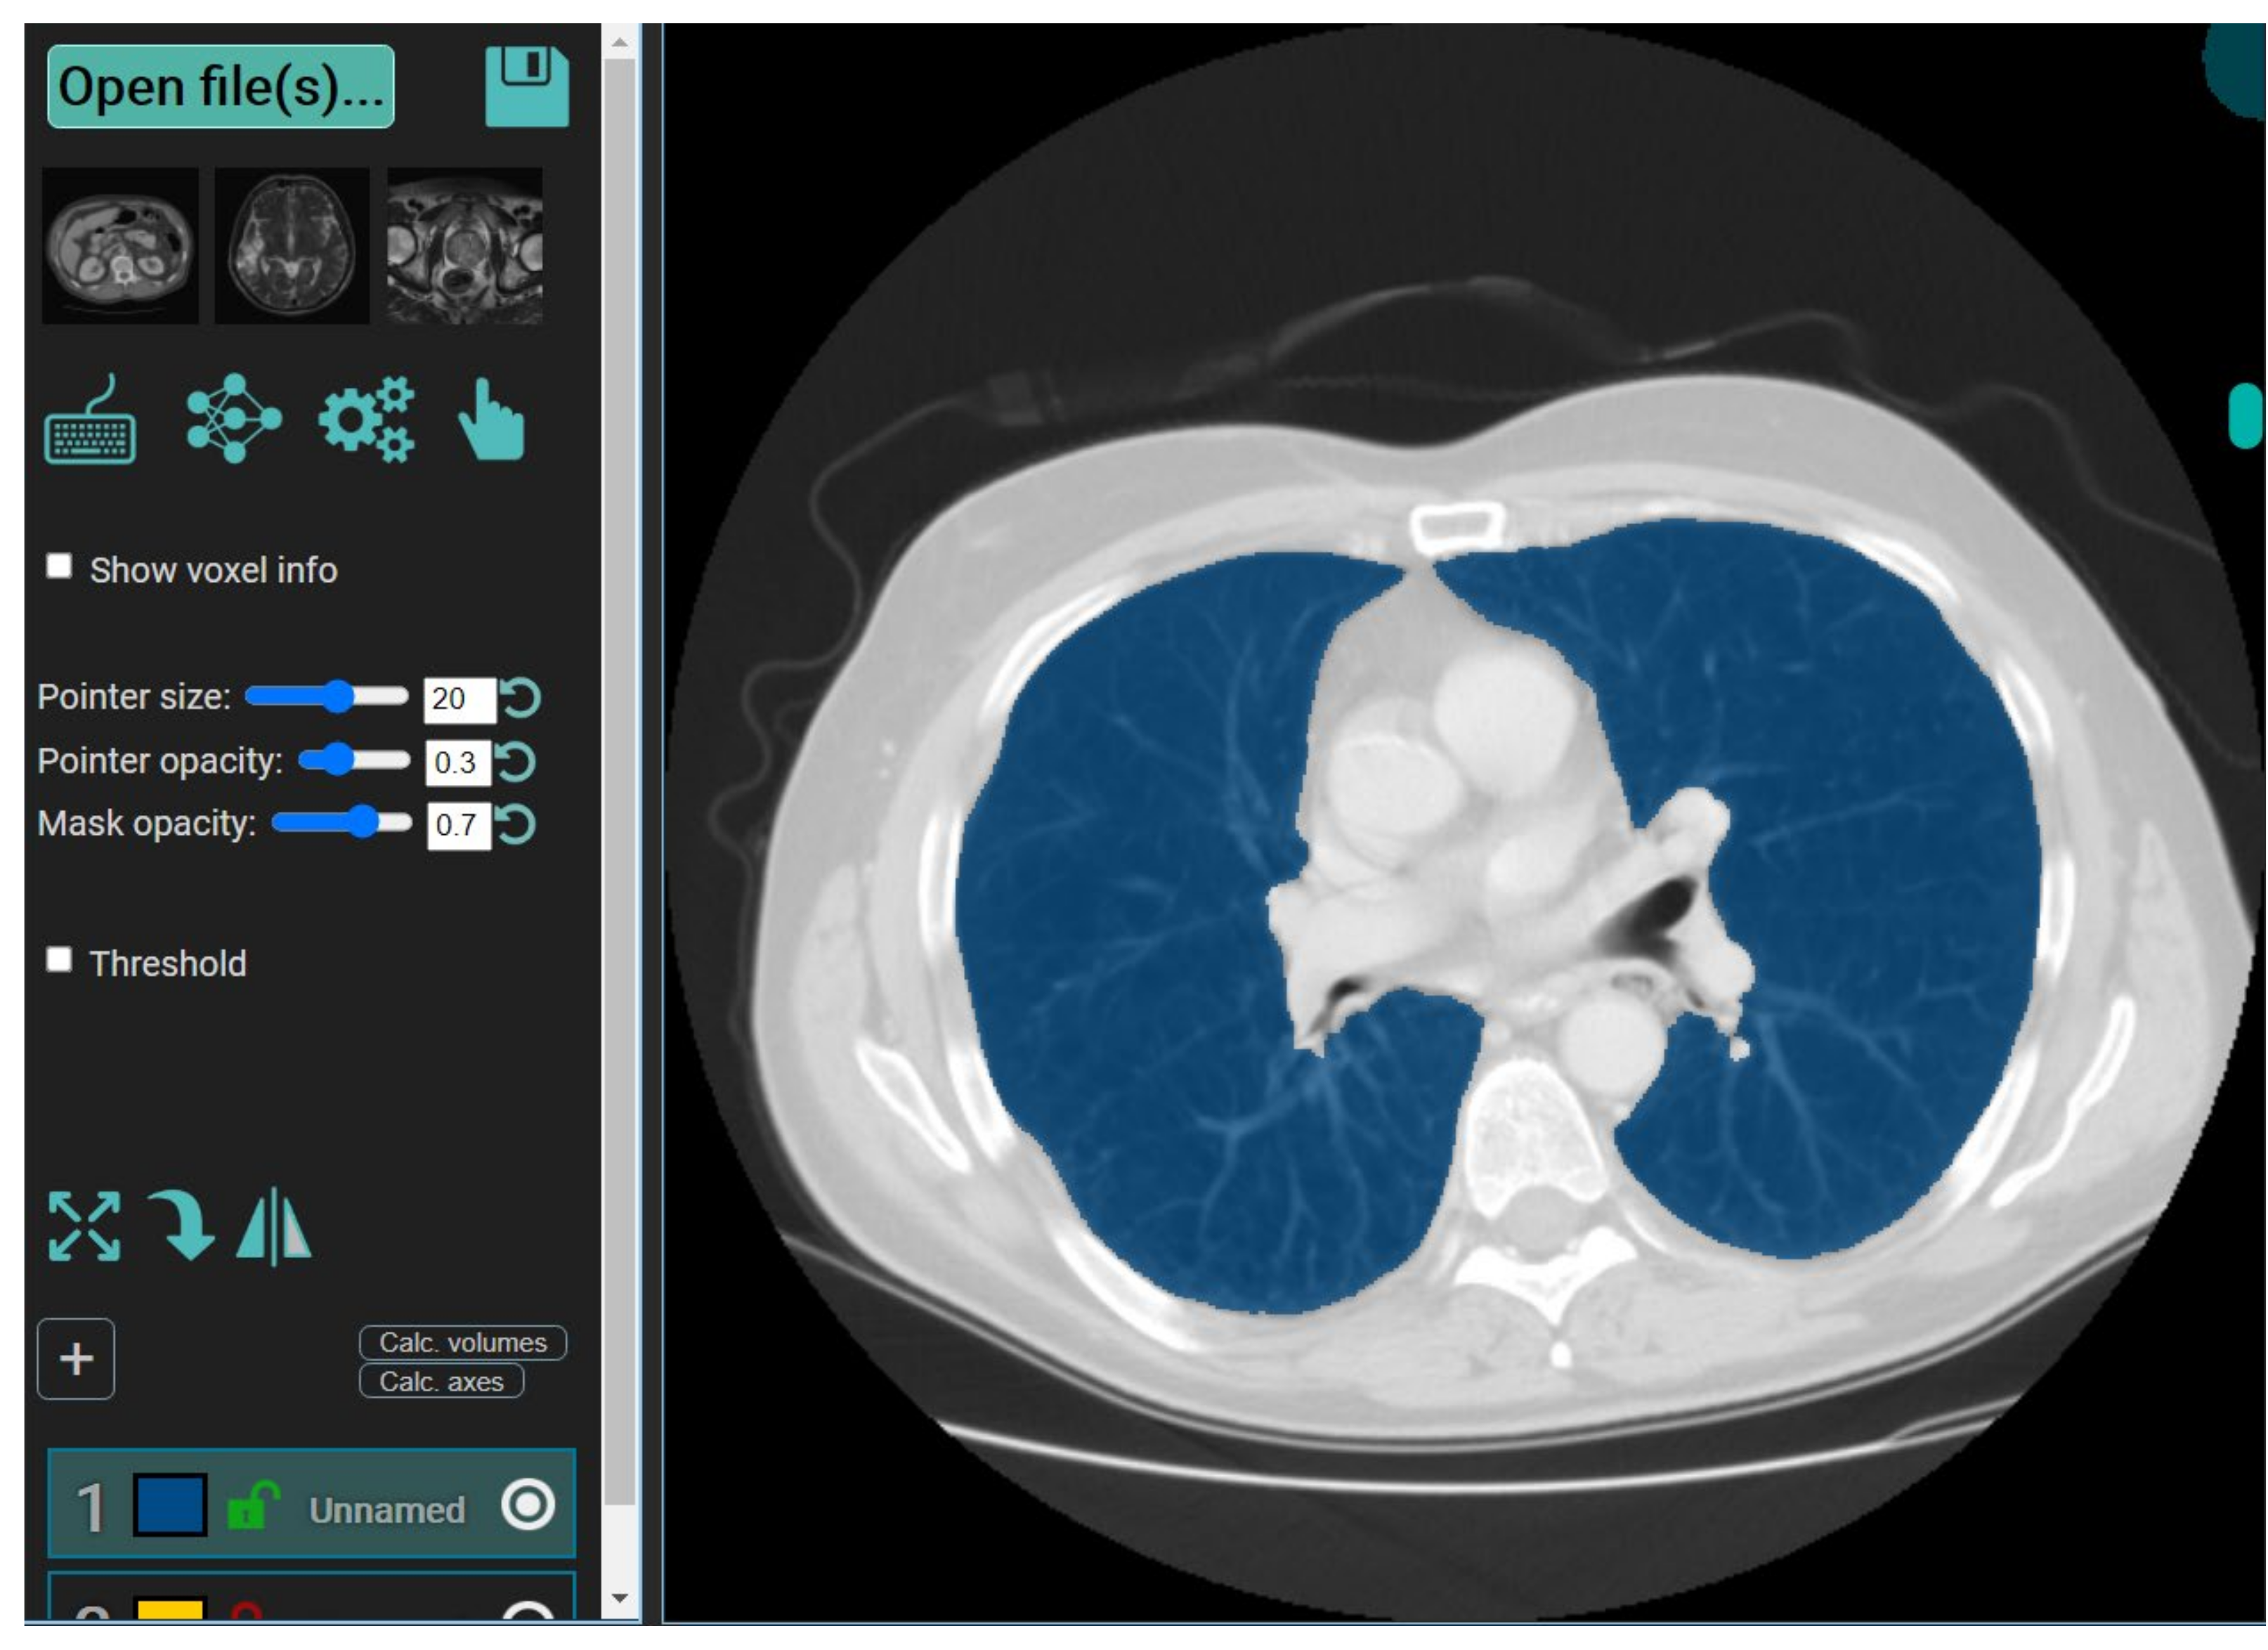

3.2.7. MedSeg—A Web-Based AI Segmentation Tool

4. Results and Performance Evaluation